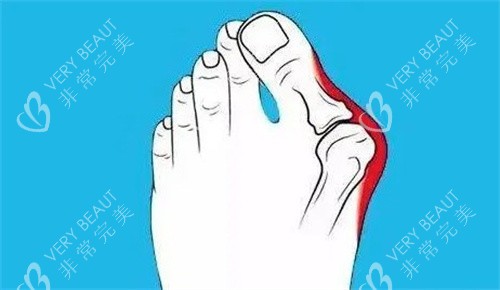

我今年28岁,从高中穿小皮鞋开始,左脚拇指就慢慢往外翻,后来右脚也跟着跑偏。夏天不敢穿凉鞋,走路久了骨头磨得生疼——这大脚骨,真成了我藏在鞋里的秘密痛。

为了确认,我又跑了两家医院。一家说要切开5cm,术后得躺半个月;另一家医生说得打钢钉,我一听就怕了。直到见到圣嘉新的苏医生——他拿着我的X光片,用铅笔在脚上画标记:你这属于中度拇外翻,用小切口技术,不用钢钉,术后当天能下地。那语气特别稳,我一下就踏实了。